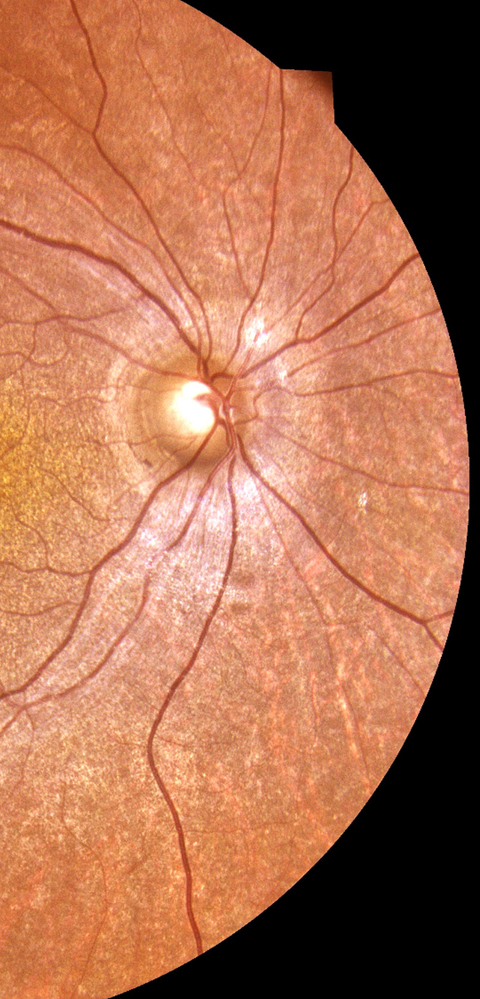

Bilateral prepapillary vascular loops in a pediatric patient